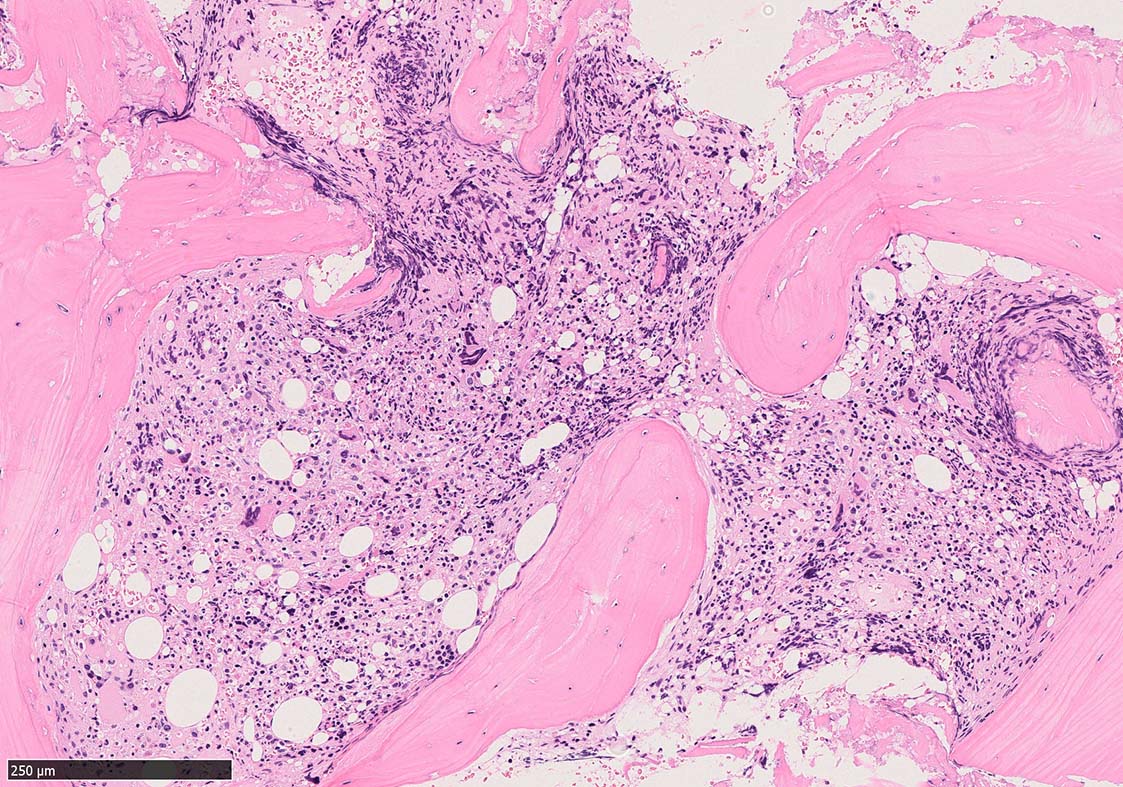

骨髄組織所見 bone marrow biopsy total 6mm in length

塗銀染色